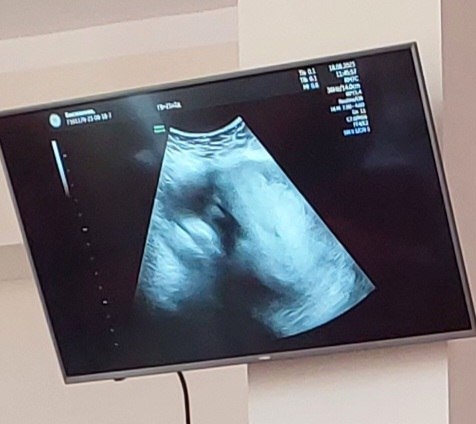

Облыстық перинатальдық орталығында 2023 жылғы 17 тамыз күні  Россия мемлекетінің мамандары: Мәскеу қаласының ​ штаттан тыс бас акушер-гинекологы Мартиросян Сергей Валерьевич, штаттан тыс бас мамандар: УДЗ дәрігерлер Перевозкина Ольга Владимировна мен Смирнова Дарья Сергеевнаның ​ қатысуымен, ​ «Акушериядағы скринигтік технологиялар» тақырыбындағы шеберлік ​ класстар басталды. Дәріс 20 тамызға дейін жалғасады.

Мастер классқа УДЗ мамандарымен қатар, акушер гинеколог дәрігерлер де қатысып, білімдерін жетілдіруде.​ Дәріскерлер қатысушыларға ​ ұрықтың хромосомалық патологиясын, туа біткен даму ақауларын ерте анықтауға және диагностикалауға, генетикалық хромосомалық, анатомиялық бұзылуларды емдеуге және түзетуге келмейтін, ауыр өліммен аяқталатын балалардың туылуын алдын алуға бағытталған​ скрининг бойынша жаңа ақпараттарды клиникалық жағдайлармен ұштастыра отырып жеткізуде.

Біздің Перинатальдық орталықта ұрықтағы туа бітті кінәраттарға скрининг жүргізіледі, яғни  құрсақтағы шаранада түрлі кеселге күдігі бар көрсетілімдермен жіберілген жүкті әйелдер қаралады. Аталған шеберлік дәрістер біздің мамандардың перинаталдық сырқаттанушылық пен туа біткен даму ақауларды төмендету бағытындағы жұмысында маңызды орын ​ алары анық.. ​ ​ ​